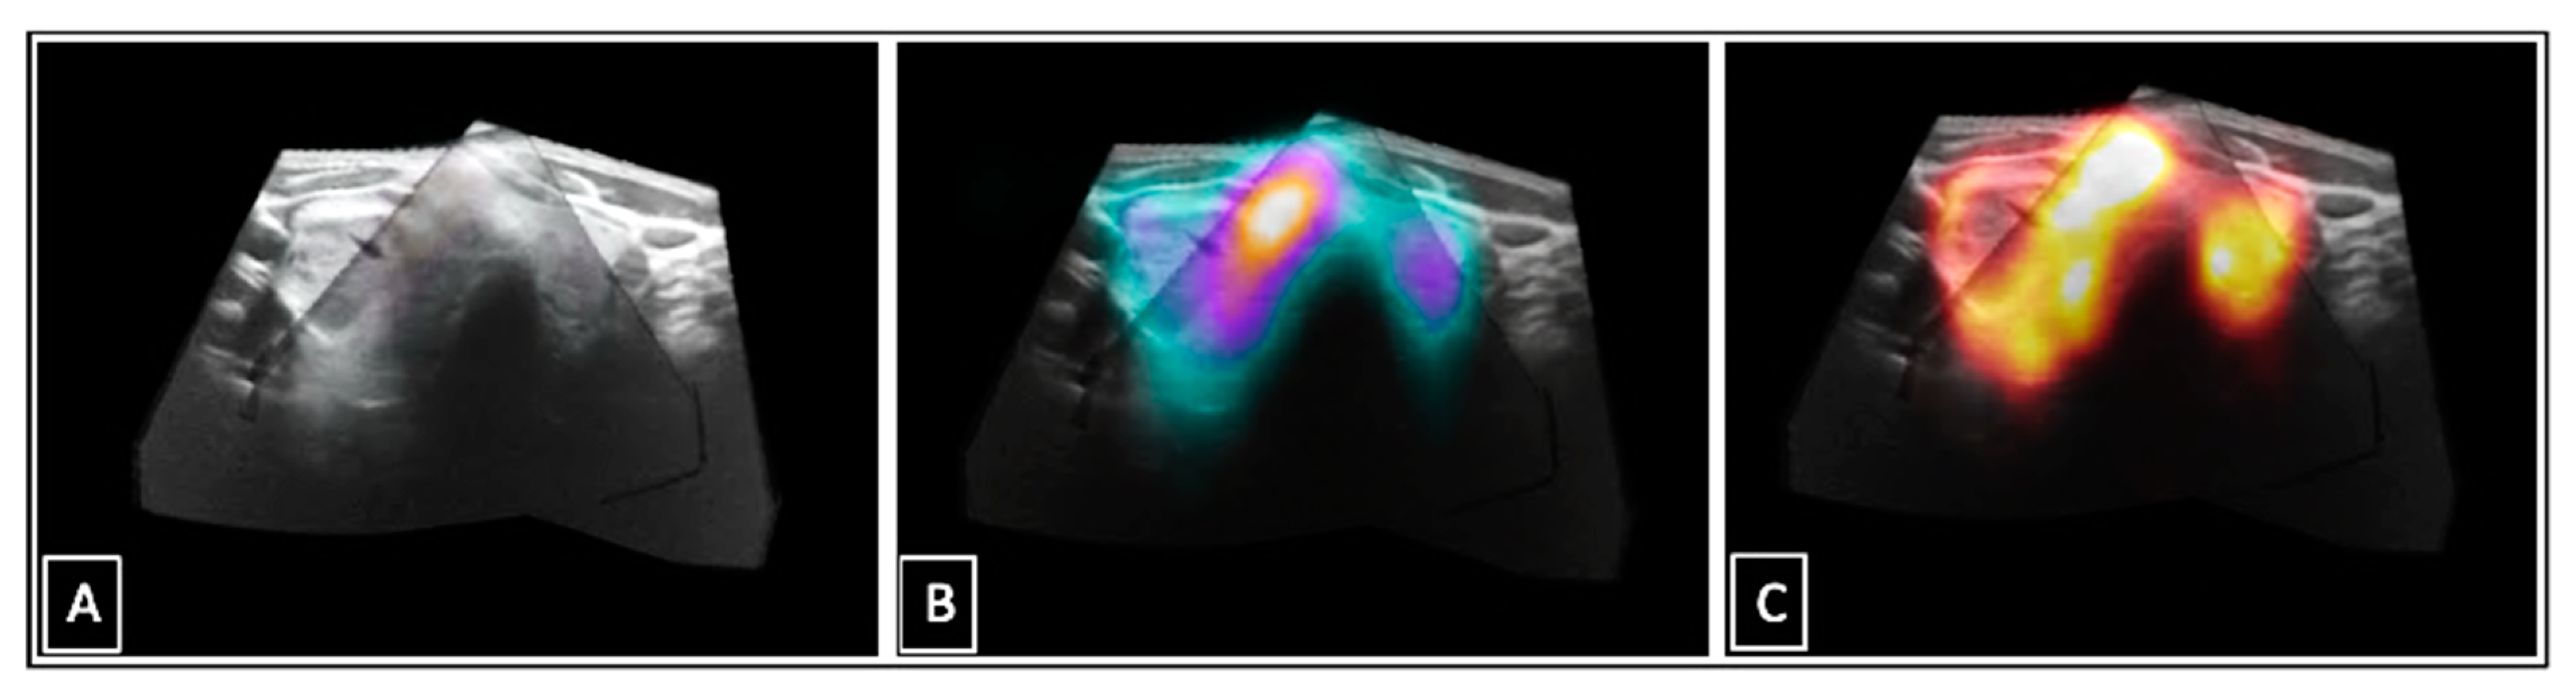

The methodological approach of US stitching has also been investigated in other disciplines, e.g., gynaecology, echocardiography, oncology, and ophthalmology [27,28,29,30]. A common goal is to optimize the image assessment with the help of an extended FOV, resulting in one comprehensive 3D-US data set of the area of interest (in this case the entire thyroid gland). Important advantages are the possibilities to export and archive the acquired 3D-US data sets, allowing for retrospective reviewing, post-processing, post-hoc volume analyses, and secondary fusion with other 3D modalities [17]. The stitched 3D-US data sets of the entire thyroid gland can theoretically be fused with any other 3D images, e.g., 99m-technetium-pertechnetate- or I-123-SPECT(/CT) data (Figure 9). In contrast to I-124-PET/CT (~6.5 mSv), 99m-technetium-pertechnetate- or I-123-SPECT scans can be performed immediately after the standard planar scintigraphy without additional radiation exposure [31]. This can be very helpful for the functional assessment of thyroid nodules in cases of unclear conventional diagnostic results. Previous studies addressed this aspect for 99m-technetium-pertechnetate SPECT/US and I-124-PET/US fusion imaging and demonstrated relevant diagnostic benefits. However, so far PET/US and SPECT/US fusion imaging have mainly been reported in the context of real-time applications, but not for a secondary fusion approach.

Figure 9.

Stitched 3DsnUS data set of a thyroid gland (A); secondary 99m-technetium-pertechnetate-SPECT/US image fusion (B); secondary I-124-PET/US image fusion (C).